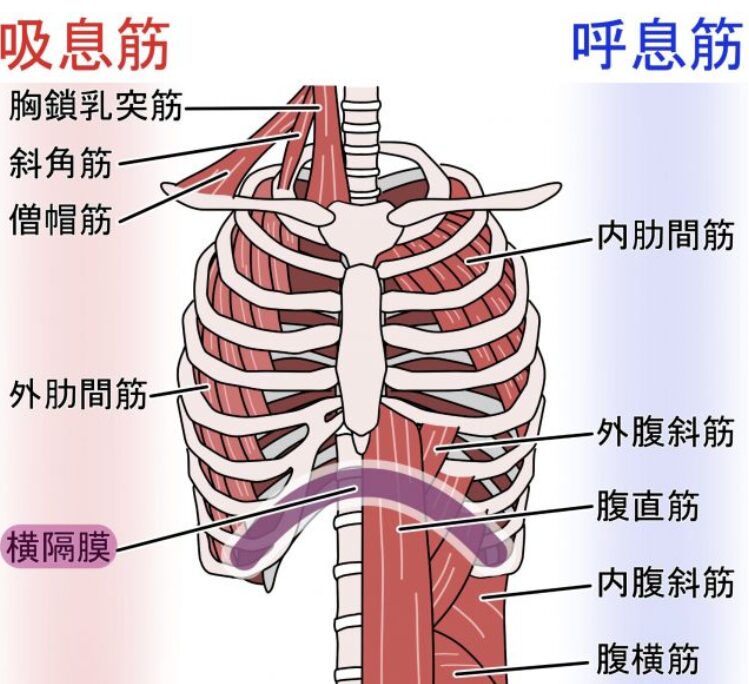

役割1:呼吸の主役

呼吸のメカニズム

息を吸う時:

- 横隔膜が収縮(力が入る)

- ドーム型が平らになるように下がる

- 胸腔(肺のスペース)が広がる

- 肺に空気が入る

息を吐く時:

- 横隔膜が弛緩(力が抜ける)

- ドーム型に戻る

- 胸腔が狭くなる

- 肺から空気が出る

私たちは1日に約2万回呼吸をしています。つまり、横隔膜は1日2万回も動いている筋肉なのです。